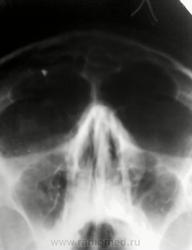

№1. Снимки выполненны в один день.

В пазухах ничего суперплохого не видно, а вот инородное тело в проекции правой лобной пазухи?

фронтит и в проекции правой фронтальной пазухи инородное тело металлической плотности

Ранений в анамнезе нет. По медиальным отделам полностью согласен, тоже рекомендовал дообследование. Мне это инородное тело кажется похожим на пломбировочный материал. Возможна ли такая миграция в лобную пазуху?

1. Это инородное тело металической плотности.

2. Боковую проекцию))))вот тогда и решим, в лобной ЧАСТИ оно...или в затылочной.

Инородное тело здесь в лобной обл. Может быть даже в лобной кости. Тут 2 же проекции.

Явно-дробь 0,5, лобную пазуху действительно нужно смотреть на боковом, а лучше КТ. Но "катаральные" пазухи-наши ЛОРы так не любили, что мы выставляли фронтиты и верхнечелюстные синуситы без тотального затемнения и уровней жидкости, что такие диагнозы, как "катаральный" синусит-это исключительно их парафия.

Пациент прошел МРТ патологии ППН не выявлено. Инородное тело отсутствует.

Хоть я и был уверен что артефакт не мог повториться в двух проекциях в одном и том же месте-> артефакт.